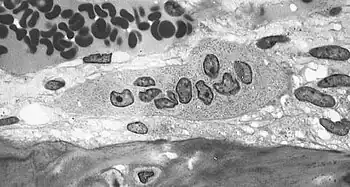

Illustration showing bone remodelling cycle Osteoclast, with bone below it, showing typical distinguishing characteristics: a large cell with multiple nuclei and a "foamy" cytosol.

Osteoclast, with bone below it, showing typical distinguishing characteristics: a large cell with multiple nuclei and a "foamy" cytosol.